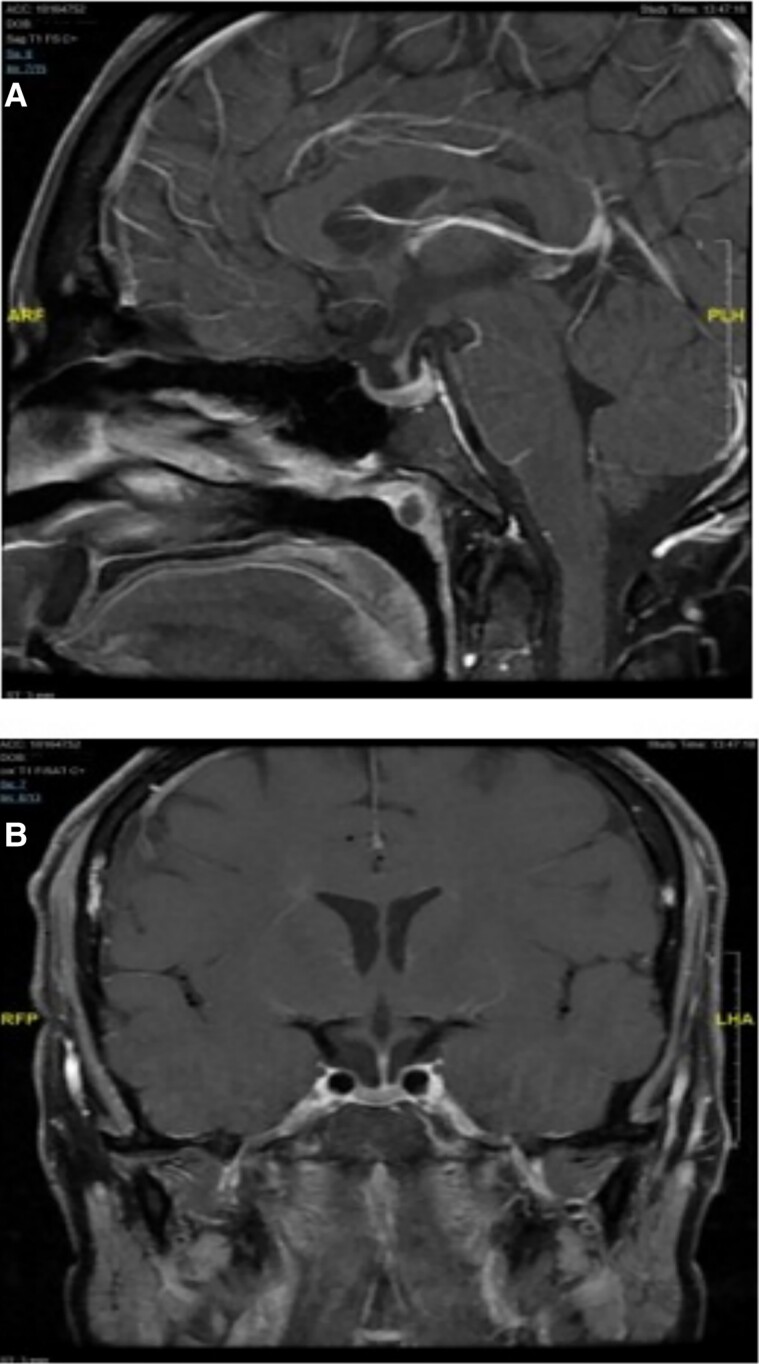

Thyrotroph hyperplasia is commonly present but remains largely undiagnosed in primary hypothyroidism. It is easily reversible with thyroid replacement therapy. If imaging is performed prior to biochemical evaluation, then patients may undergo pituitary surgery unnecessarily. We present the case of a 30-year-old man with thyrotroph hyperplasia caused by profound primary hypothyroidism leading to hypopituitarism that resolved after levothyroxine replacement therapy. We will discuss the current literature regarding pituitary hyperplasia in primary hypothyroidism in adults.

Abstract Image